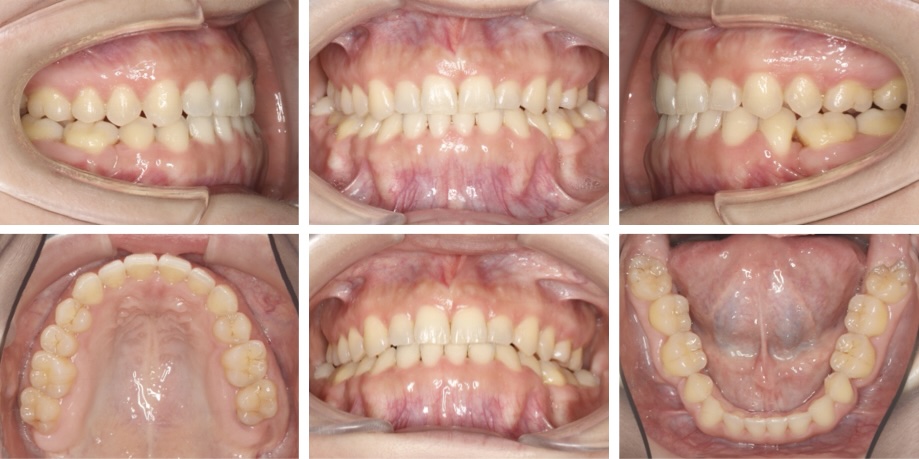

初診時、乳歯が上顎に1本と下顎に2本残っており、同部位の永久歯が生まれつき認められませんでした。乳歯はいずれも永久歯よりも低い位置に埋まっており、それに伴い両隣の永久歯が倒れ込んでいる状態でした。

治療では、残存する乳歯3本と右上の親知らずを1本抜歯して治療を行いました。当初、歯科矯正用アンカースクリューの使用を検討していましたが、患者さんが取り外しのできるゴムの使用を頑張ってくださったため、スクリューを使うことなく予定取りの治療を終えることができました。

大変難しい治療ではありましたが、患者さんのご協力のお陰で、もともとバランスのとれていた口元は変化させず、かみ合わせをしっかり改善することができました。 患者さんは今まで、乳歯の部分はデンタルインプラントやブリッジなど人工物をいれる方針にするか長年悩まれていたそうですが、治療後に「思い切って矯正治療を頑張ってよかった」とおっしゃっていました。